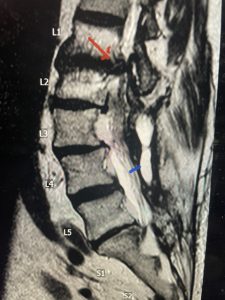

The next patient is a 71 year-old male with a two-year history of low back pain and lower extremity pain, numbness and weakness. His left leg was worse than the right. He had had five epidurals with no improvement. He also had tried physical therapy and medicines but nothing helped. He also felt that over the last three weeks he had gotten worse. He also had recently had some decreased sensation of bladder fullness and difficulty with bowel movements. MRI revealed a very tight L2-5 stenosis with an extruded L3-4 disc fragment (Fig 3).

(Figs 3a) Sagittal (a) and Axial (b) T2-weighted lumbar MRI demonstrating severe spinal stenosis L2-5 (arrow)and extruded disc at L3-4 on axial image (arrow)

He had concentric severe stenosis with severe compression of the lateral recess and foramen at L3-4 secondary to the superimposed disc herniation. The fact that he had gotten worse with subtle cauda equina features with an extremely tight canal, he underwent a decompressive laminectomy. We also augmented his laminectomy with an in situ fusion from L3-5 as he was relatively young, with more time to reform arthritis, and had been unstable enough to extrude a disc fragment. By placing “bone dust” or bone material along the sides of the spine, specifically laying it across the transverse processes after they have been drilled to bleeding bone, you provide an environment where bone formation is induced to connect the segments, stabilize them, and thereby reduce the signal to make more arthritis as that signal is still present despite the laminectomy. What was interesting was that we encountered a large extruded disk fragment that was significantly contributing to his compression which is often not found in patients in this age bracket. Post operatively he had much improvement of leg pain.